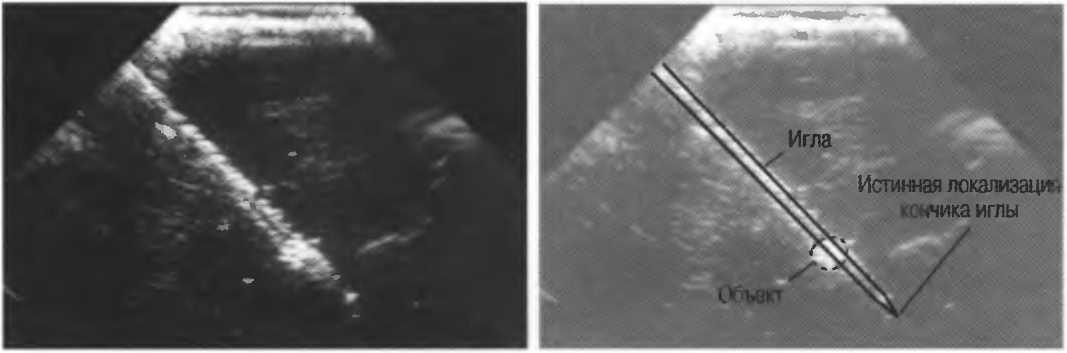

На практике, наиболее значимые в клиническом плане артефакты возникают при проведении биопсии или аспирации под контролем ультразвука. До тех пор пока кончик иглы не появится в плоскости сканирования на экране, он не будет визуализироваться, и может создаться ложное представление о том, что игла значительно короче (рис. 21в).

Рис.21 в. Изображение иглы в емкости с водой. Слева игла находится в плоскости сканирования не полностью, в результате чего выглядит короче, чем есть на самом деле (крестик определяет реальную глубину проникновения иглы). Справа игла визуализируется полностью.